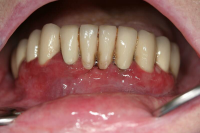

Gingivit är tandköttsinflammation som visar sig genom marginal blödning vid sondering, men där tanden ej har någon förlust av käkbensfäste.

Diagnosen gingivit används vid tänder med marginal inflammation och blödande tandkött, men ingen förekomst av marginal benförlust. Fickdjup 1–3 mm, pseudofickor kan förekomma upp till 5 mm.

Ödematös, rodnad och blödande gingiva.